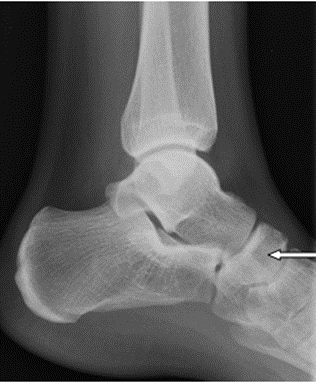

Na radiogramie uwidoczniono

Ilustracja do pytania 3

A. złamanie podstawy I kości śródstopia.

B. paluch koślawy (hallux valgus) stopy prawej.

C. paluch szpotawy(hallux varus) stopy prawej.

D. złamanie guzowatości V kości śródstopia.